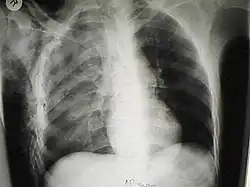

Les cas importants d'emphysème sous-cutané sont faciles à diagnostiquer en raison des signes caractéristiques de l'affection. Dans certains cas, les signes sont subtils, ce qui rend le diagnostic plus difficile. L'imagerie médicale est utilisée pour diagnostiquer la maladie ou confirmer un diagnostic établi à l'aide de signes cliniques. Sur une radiographie du thorax, l'emphysème sous-cutané peut être vu comme des stries radiotransparentes dans le modèle attendu du groupe de muscles principaux du pectoral. L'air présent dans les tissus sous-cutanés peut interférer avec la radiographie du thorax, ce qui peut masquer des affections graves comme le pneumothorax. Elle peut également réduire l'efficacité de l'échographie thoracique. D'autre part, comme l'emphysème sous-cutané peut être visible sur les radiographies du thorax avant un pneumothorax, sa présence peut être utilisée pour déduire celle de cette dernière lésion. L'emphysème sous-cutané peut également être observé sur les scanners, les poches d'air apparaissant comme des zones sombres. Le scanner est si sensible qu'il permet généralement de trouver l'endroit exact d'où l'air pénètre dans les tissus mous. En 1994, M. T. Macklin et C. C. Macklin ont publié d'autres aperçus sur la physiopathologie du syndrome de Macklin spontané survenant à la suite d'une grave crise d'asthme. La présence d'un emphysème sous-cutané chez une personne qui semble très malade et fébrile après une crise de vomissements suivie d'une douleur thoracique gauche est très évocatrice du diagnostic du syndrome de Boerhaave, qui est une urgence vitale causée par une rupture de l'œsophage distal. L'emphysème sous-cutané peut être une complication de l'insufflation de CO2 avec la chirurgie laparoscopique. Une augmentation soudaine du CO2 en fin de marée après la hausse initiale qui se produit avec l'insufflation (les 15-30 premières minutes) devrait faire suspecter un emphysème sous-cutané. Il est à noter que l'oxymétrie de pouls et la pression des voies aériennes ne varient pas dans l'emphysème sous-cutané, contrairement à l'intubation endobronchique, au capnothorax, au pneumothorax ou à l'embolie au CO2.